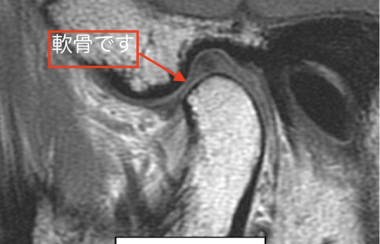

顎関節症治療とMRI撮影

名取歯科医院で治療を受けていただく場合には、MRI撮影が必須になります。

肘や膝に問題があった場合、整形外科では必ずにMRI撮影をするはずです。なぜならば関節を治療するためには体の内側の骨や軟骨の状態を知らなくてはならないからです。そして顎関節は人間の関節の中の一つです。

顎関節症は肘や膝と同じ関節障害なのですが、多くの歯科医院では整形外科のように原因究明にMR撮影を選択することがまずないのが現状です。しかし、名取歯科医院では治療のためにはMRI撮影が必要だと考えています。

MRI撮影により顎関節の中の軟骨の位置を知ることで、適正な咬み合わせの位置を決定することが出来るのです。

根本原因である顎関節の不調を解決するには、歯や口から始めるのではなく「関節を中心に考える整形外科的アプローチ」が大切なのです。

そのためにMRIでの撮影は必須であると名取歯科医院では考えております。